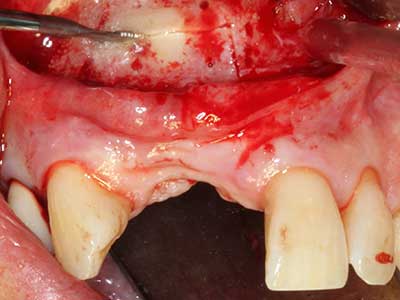

Indikation: Parodontaltherapie

Marginale Parondontalerkrankungen stellen im fortgeschrittenen Alter den Hauptgrund für Extraktionen dar. Sie basieren im Wesentlichen auf einer bakteriellen Besiedlung der Zahnfleischtasche und hierdurch bedingten Entzündung mit konsekutivem Verlust des Zahnhalteapparates. Die Ausbildung subgingivaler Biofilme und Konkremente stellt einen wesentlichen ätiologischen Faktor für den marginalen Knochenabbau dar, so dass ihrer Entfernung eine wesentliche Bedeutung in der Therapie zukommt (Drisko 2014, Plessas 2014).

Zur Behandlung einer marginalen Parodontitis lassen sich eine initiale und chirurgische Therapiephase unterscheiden. Neben der Mundhygieneinstruktion und -motivation sollte in beiden Phasen eine suffiziente Reinigung der Wurzeloberfläche erfolgen, wobei im regenerativen Setting zumeist ein offener Zugang gewählt wird. Die Reinigung der Wurzeloberfläche kann durch die Verwendung spezieller Ansätze auch piezochirurgisch erfolgen, wobei unterschiedlich gebogene Instrumente auch schlecht zugängliche Bereiche wie Furkationen erreichen. Die systemimmanente Wasserkühlung spült dabei die gelösten Konkremente und Bakterien aus der Tasche. Um zusätzlich die Abtragung von Zahnhartsubstanz zu minimieren, wurde bei speziellen Systemen wie dem Piezomed ein Applikations-Feedback eingebaut. Hierbei wird die Abtragungsleistung konsequent reduziert, je mehr Druck auf den Parodontalansatz ausgeübt wird.